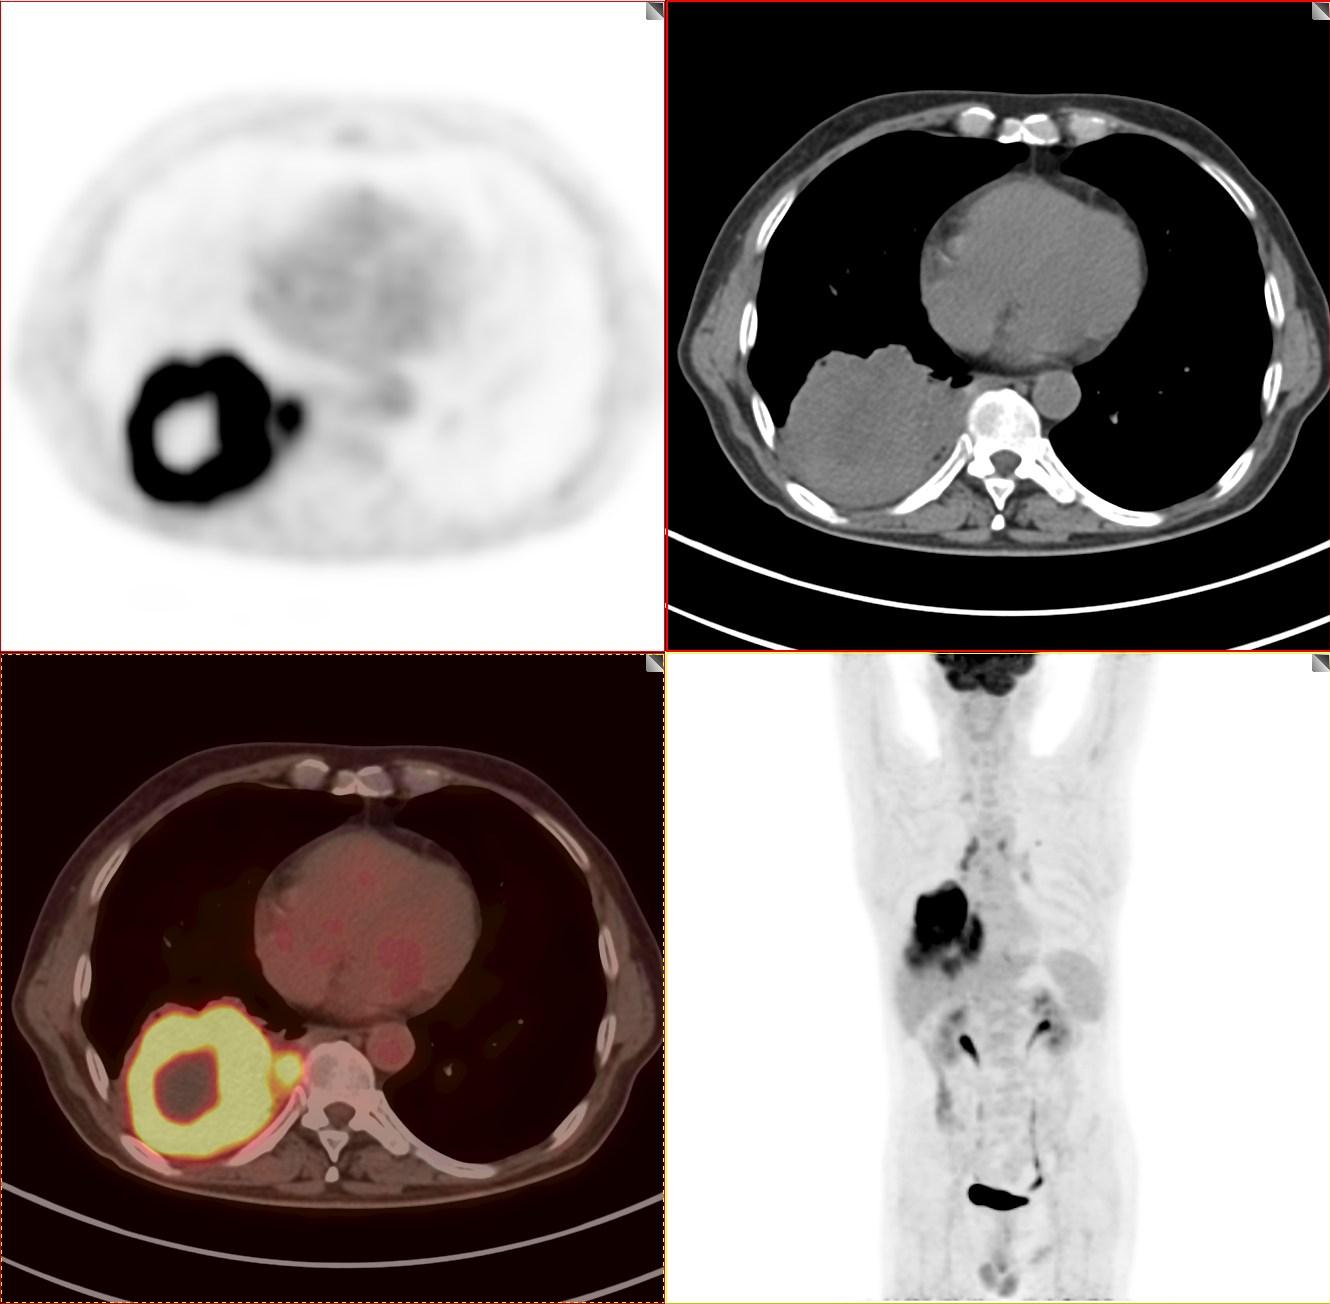

今天和大家分享的是一位晚期肺癌的患者,2021年8月份来接诊。男性 67岁老人,由于平时不注重体检,发现咳嗽伴痰中带血才来就诊,CT发现肺内占位,肿瘤指标多项升高。发现时病灶最大径已经超过8cm,病灶累及相邻胸膜,肿瘤T分期达到T4期,相邻胸膜受到明显累及,M分期达到M1a,淋巴结转移未知,一起来看看这个巨大的肿块。

软组织肿块,最大径超过8厘米

这个肿块CT诊断诊断不难,能明确是肺癌,但下一步处理必须进行肿瘤分期。一定要明确全身情况,进行肿瘤分期。通过第一次PET/CT检查的图像,我们做一个肿瘤分期,看看这个病变有没有转移。肺癌包括其他恶性肿瘤治疗,第一步就是进行肿瘤分期。

病灶FDG代谢明显增高

我们看着一团"火"一样的病灶就是这个肺癌,由于肿瘤生长速度快,血供跟不上,中心出现液化坏死区,中央出现一个“窟窿”。

病灶累及胸膜

胸腔少量积液

上面两张图提示病灶累及胸膜胸腔出现少量积液。非常幸运的是该患者没有出现明显的区域淋巴结转移及远处转移。由于病灶太大,相邻胸膜受到累及。依据NCCN、AJCC最新指南我们进行肿瘤分期。

T分期:T4

N分期:N0

M分期:M1a

综合分期:Ⅳa期